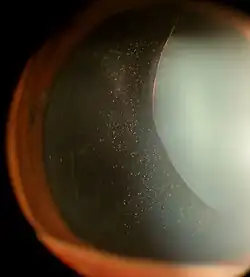

| Ectopia lentis in a patient with Marfan syndrome. Zonular fibers are visible. | |

Ectopia lentis is a displacement or malposition of the eye's lens from its normal location. A partial dislocation of a lens is termed lens subluxation or subluxated lens; a complete dislocation of a lens is termed lens luxation or luxated lens.